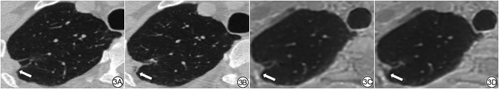

以往的研究[21,23,26]已经表明,通过形态学特征对肺结节进行无创恶性危险分层是必要的;Lung-RADS等指南[27]也提到需要关注结节的放射学特征有助于随访管理。WIELPÜTZ等[20]对51例病人的119个肺结节进行了UTE MRI与CT的对照研究,研究提示:虽然UTE MRI图像会高估结节边缘光滑程度,但是,对于肿瘤边缘特征和内部结构均有较好的识别。研究中,两名医生在UTE MRI上对结节恶性特征认知的敏感度不同,但特异度均较高;其中,空泡征的检出敏感度和特异度均较高,胸膜牵拉的识别敏感度最高,支气管血管束增厚的识别敏感度最低;但两名医生对分叶征的认知能力差别很大,敏感度分别为70.6%和54.9%。另外,两名医生对粗毛刺和细毛刺的鉴别能力均稍差;由此可见,UTE MRI对肺结节形态学的诊断能力接近CT参考标准。图3展现了一例右肺上叶部分实性结节的胸膜牵拉征象在UTE MRI和CT图像中的表现。